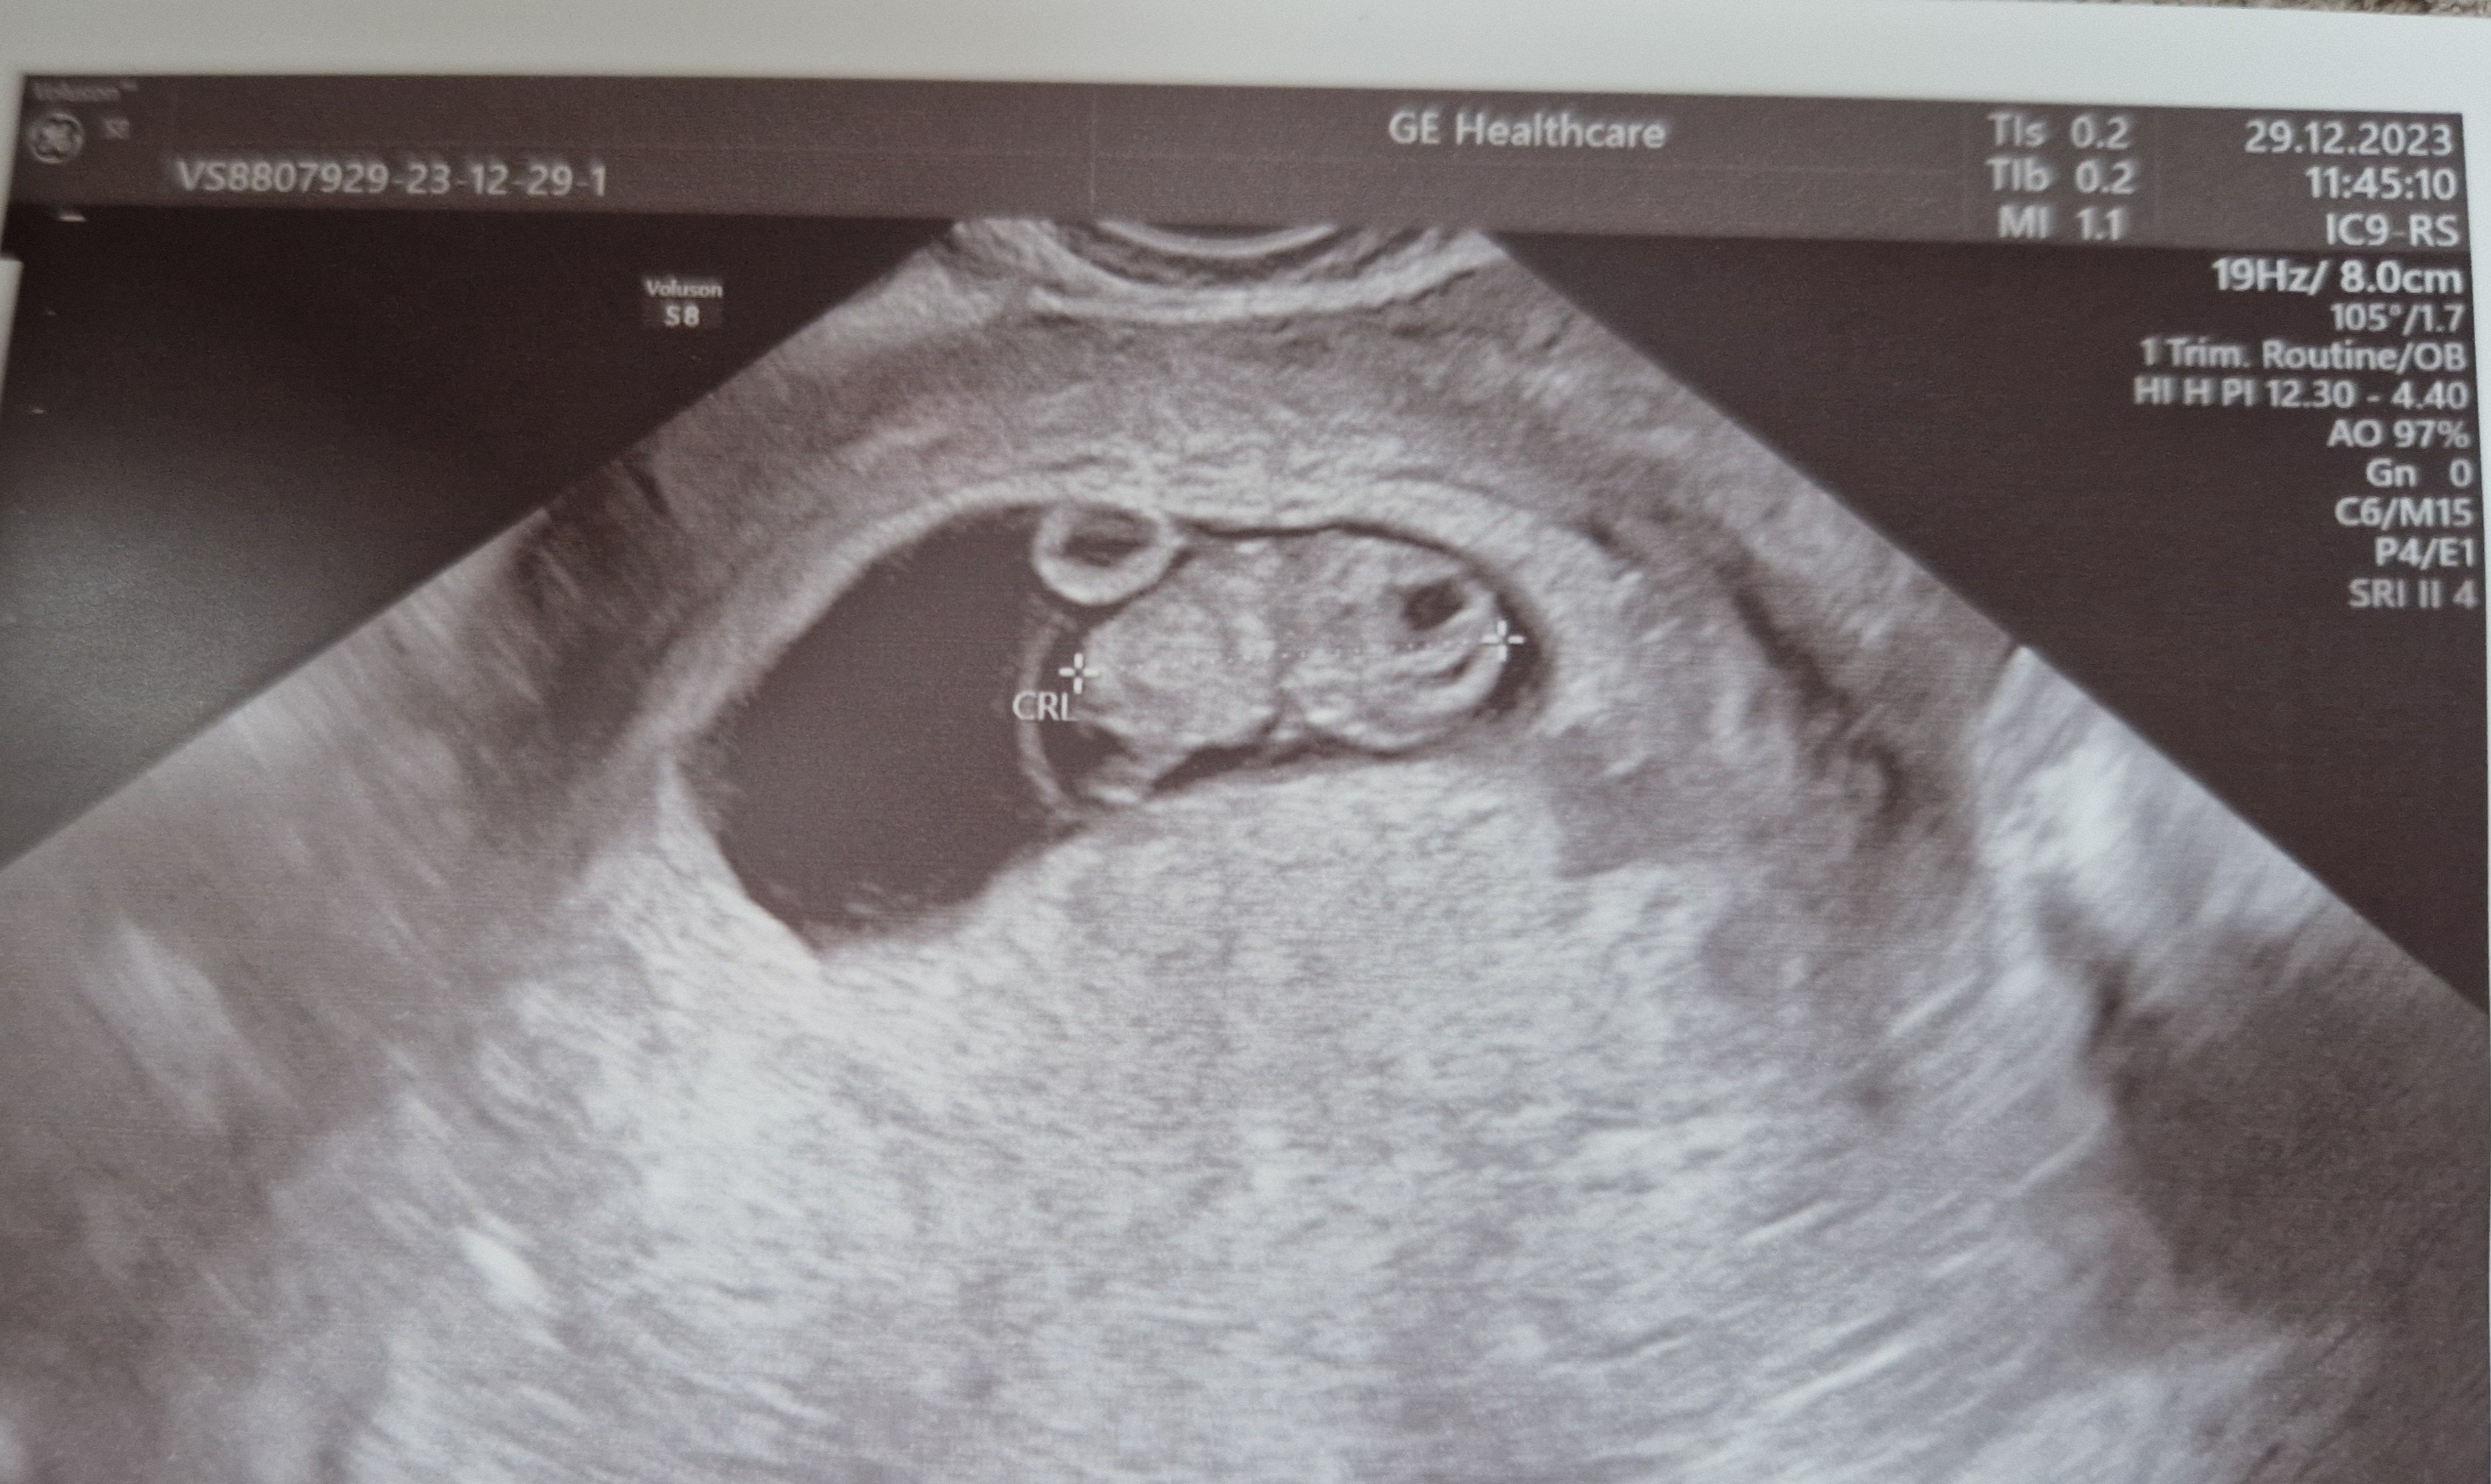

Mój od początku. Zawsze jak nie poszedł to coś się działo. Np dowiedziałam się o wadzie genetycznej. Pomijam to wczoraj (chociaż to potwierdza co było z córką).Dziewczyny, kiedy zabieracie mężów żeby mogli zobaczyć dziecko na usg?mój z jednej strony już by chciał ale z drugiej woli poczekać jak już będzie więcej widać niż mała kropeczka

Mój prowadzący dopochwowo robi na kozetce i zasłania parawanem a mąż / partner itd patrzy na ekran.Ja jak będzie już przez brzuch USG, bo to dopochwowe mało atrakcyjne mi się wydaje![]()

Mój bierze 300zł za wizytę. Natomiast robi usg na sprzęcie do prenatalnych i zawsze dostawałam książkę z wszystkimi wymiarami, zdjęciami itd. Mam cudowne zdjęcia córki z tych wizyt.to tak jak ja w invicie też wizyta tylko usg i omówienie (bo resztę ogarniam przez luxmed) ale to co widać na usg jest warte tego hajsu...